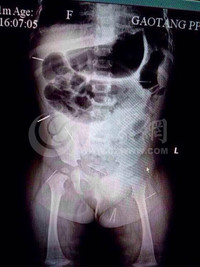

Trường hợp kì lạ này xảy ra trên người của một bé gái ở Trung Quốc. Bé gái Phạm Tử Huyên hơn 11 tháng tuổi, bố mẹ bé phát hiện trên người con mọc những chấm đỏ kỳ lạ, bé không ngừng khóc.

Kết quả khám chụp của các bác sĩ khiến ai cũng giật mình: trên cơ thể bé gái có đến 12 cây kim ở khắp cơ thể các bộ phận như ngực, mông, đùi…Do kim đã đi sâu vào cơ thể nên nhìn bên ngoài rất khó phát hiện.

Mẹ của cô bé cho biết, trước khi phát hiện ra những chấm đỏ này,khi cô cho xoa vào mông của bé, bé khóc thét lên không ngừng, khi đó ở mông bé đã xuất hiện 4 cây kim.

Tuy nhiên bố mẹ cô bé cho rằng đó là do bé nghịch ngợm nên chẳng may bị kim đâm. Cho đến nay trên cơ thể bé đã xuất hiện 12 cây kim, khiến đôi vợ chồng không khỏi nghi ngờ đó là một căn bệnh lạ.

Điều khổ tâm là khi bế em, lỡ có ai động vào bộ phận bị kim châm, bé Phạm lại khóc không ngớt. Vợ chồng cô Phạm nhìn con mà lòng đau như cắt.

Các bác sĩ tại bênh viện Tế Lỗ cho rằng, 12 cây kim hiện đã đi sâu vào cơ thể của bé, việc lấy ra là vô cùng khó khăn và họ vẫn chưa tìm được biện pháp nào.